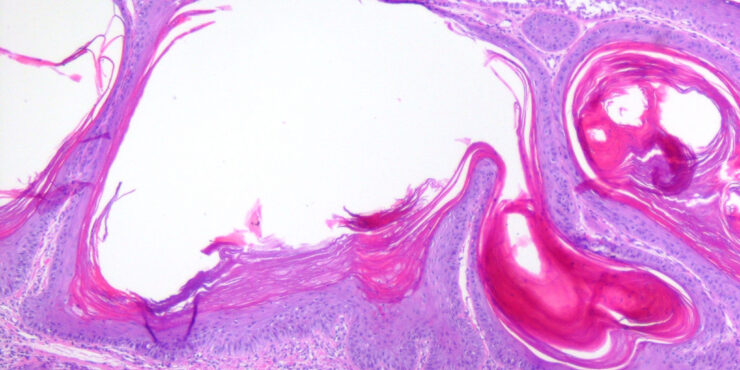

Read MoreCystic_scc = الورم الشائك الخلايا الكيسي OLYMPUS DIGITAL CAMERA OLYMPUS DIGITAL CAMERA